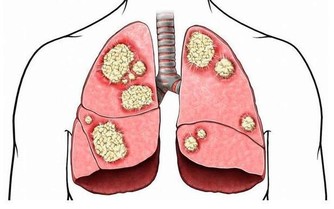

隨著生活水平的提高,人們的飲食條件越來越好,但很多人卻不注意飲食,造成了腸癌的發病機率上升。實際上,腸癌的發生跟生活方式有很大的關係,而且男性的發病機率明顯高於女性。在臨床上,腸癌在早期時症狀不明顯,即使有症狀也會被人忽視,只是感覺到身體不適,容易消化不良。

一般來說,以下異常表現的出現就是腸癌的早期症狀:

總而言之,腸癌對人體健康的影響是很大的,屬於惡性腫瘤。若平時感覺到身體不適,經常的出現便血,必須要合理的進行檢查。如果出現腸癌,也不要氣餒,不要放棄治療。在早期時,疾病可以有效控制,患者需選擇適合的治療方法,有效的緩解疼痛。千萬不要坐以待斃,放棄治療。